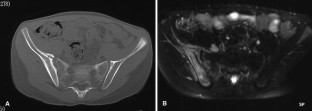

Fig. 2.